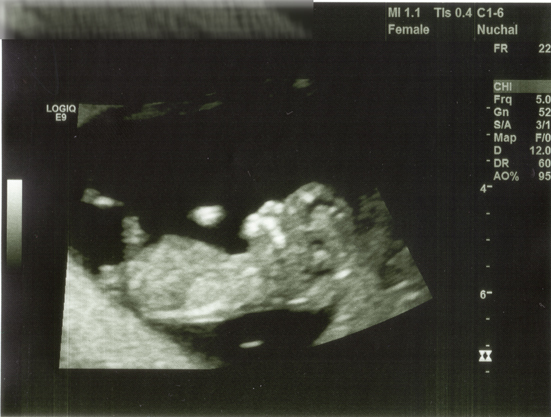

Why does our 12 week (11wk3) ultrasound say female? Obviously they haven't sexed it yet, is that the default reading until they know otherwise?

I can't imagine why you'd need to have a record of the mother's gender.

This definitely refers to you. Ultrasound machines are used for many investigations on both sexes so in the patient demographics the gender of the patient is also recorded.

The ultrasound machines require standard information like the patients sex to be entered in regardless of the scan being performed.